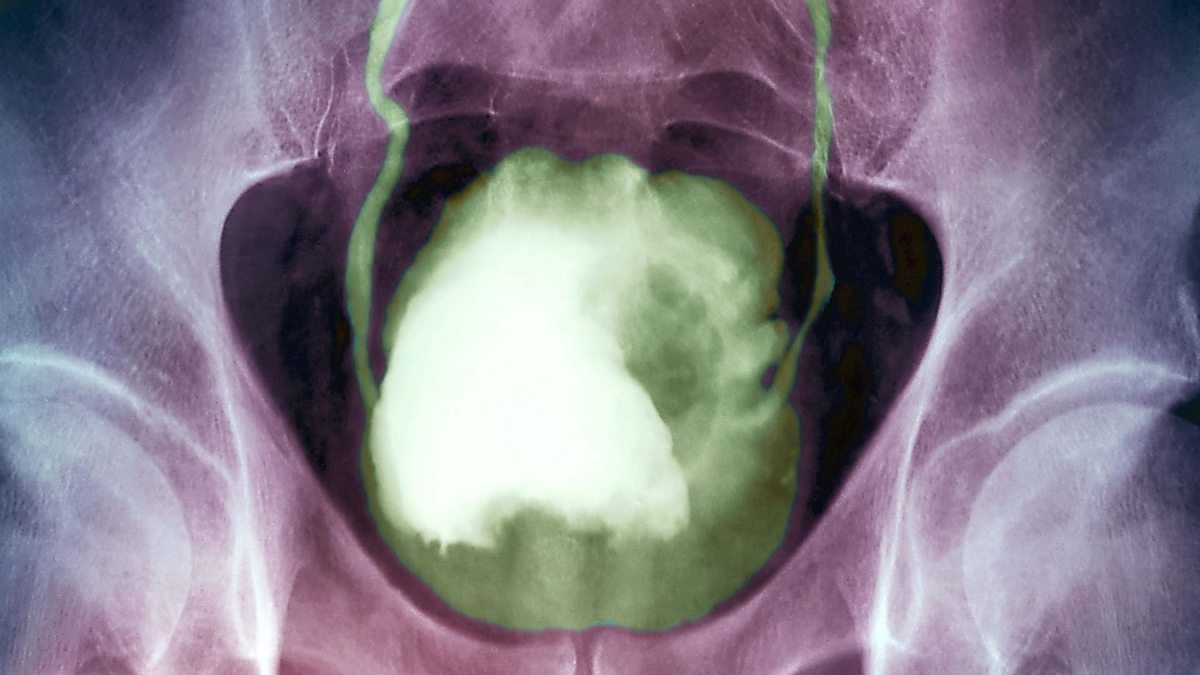

Рак 3 Стадии ФотоВыберите Ваш пол👨 👉🏻👉🏻👉🏻МУЖЧИНА👈🏻👈🏻👈🏻👩🦱 👉🏻👉🏻👉🏻ЖЕНЩИНА👈🏻👈🏻👈🏻Рак 3 Стадии Фото (143 фото)